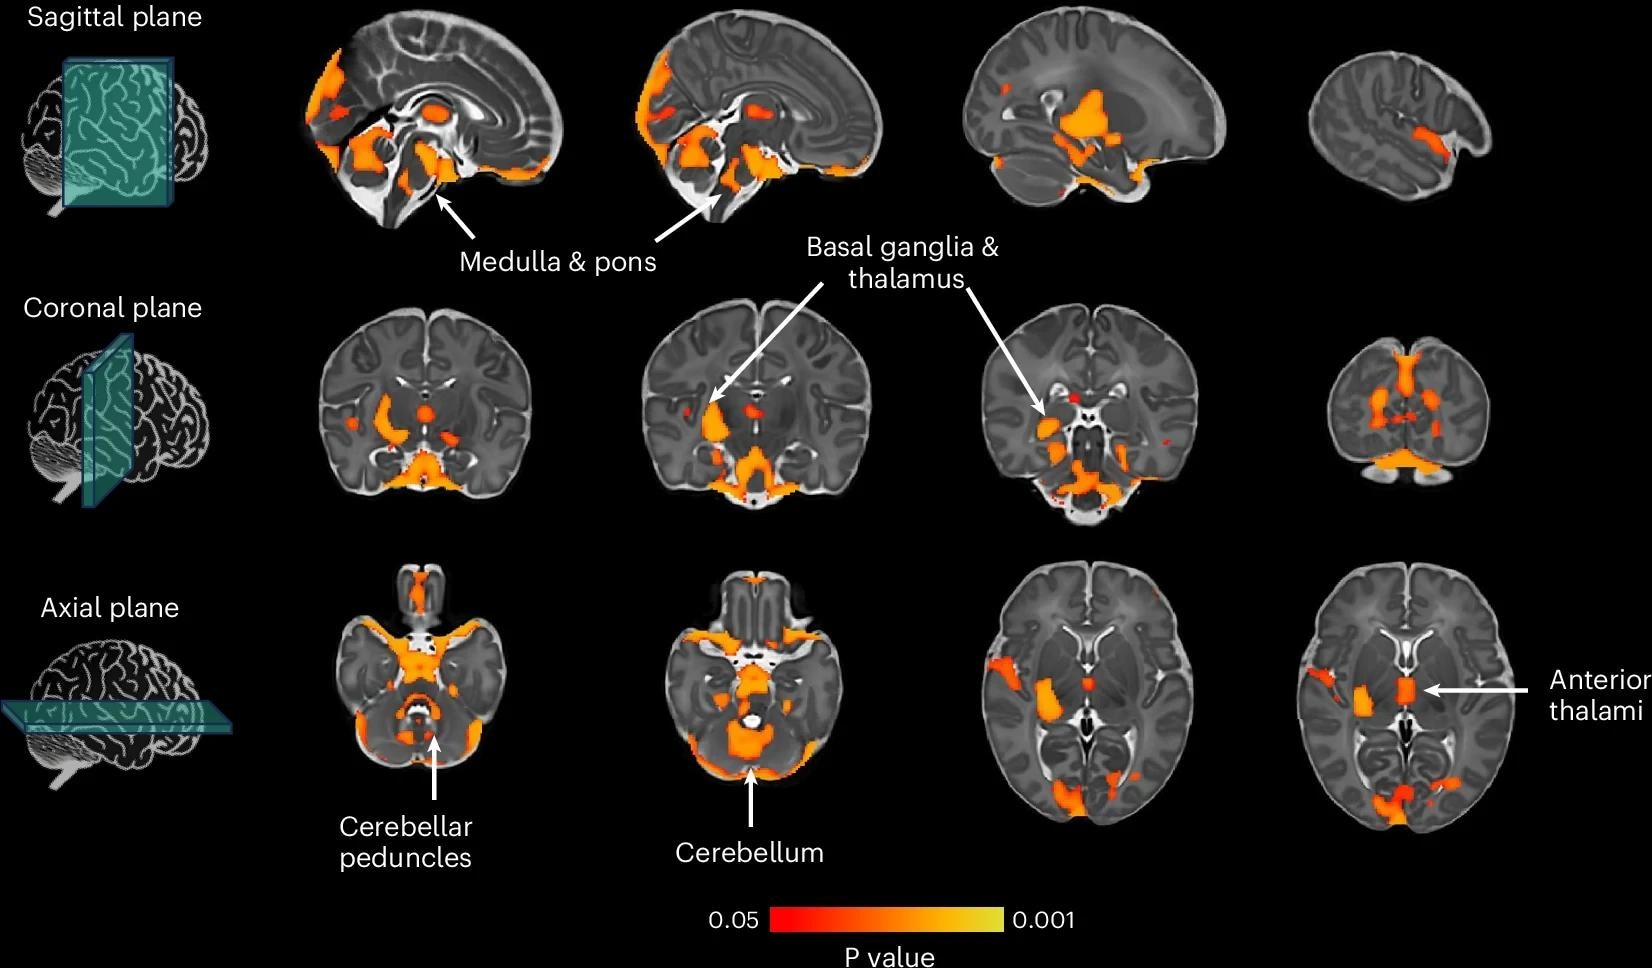

אמנם נדיר ביותר, אך לאנצפלופתיה (מצב המשפיע על תפקוד המוח) המופעלים על ידי מוטציות בגן UBA5 יש השפעות הרסניות, כאשר